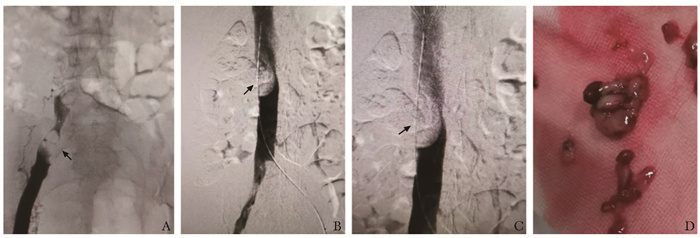

• 摘要: 低级别子宫内膜间质肉瘤(low-grade endometrial stromal sarcoma, LG-ESS)是一种罕见的子宫恶性肿瘤, 在所有子宫恶性肿瘤中占比不足1%, 目前国内外尚无关于LG-ESS导致急性完全性下腔静脉阻塞的报道。2020年11月, 北京协和医院血管外科接诊1例LG-ESS患者, 临床表现为月经紊乱、右下肢凹陷性水肿、突发恶心、少尿、肌酐升高, 影像学提示下腔静脉完全性阻塞, 通过多学科协作共同决策, 采用分期手术联合内分泌治疗成功救治该患者, 其诊疗过程体现了多学科协作在疑难重症患者诊治中的重要作用。

Abstract: Low-grade endometrial stromal sarcoma (LG-ESS) is a rare uterine malignancy, accounting for less than 1% of all uterine malignancies. And there is no literature reporting about acute obstruction of inferior vena cava (IVC) caused by LG-ESS. In November 2021, A patient diagnosed with LG-ESS was admitted to our hospital, presenting with pitting edema of the right lower limb, menstrual disturbance, nausea, oliguria andincreased serum creatinine. Imaging suggested complete obstruction of IVC cava. This difficult case was successfully treated with staging surgery combined with endocrine therapy by a cooperative multidisciplinary team (MDT). The important role of MDT in the treatment process of such a difficult and serious case was demonstrated.